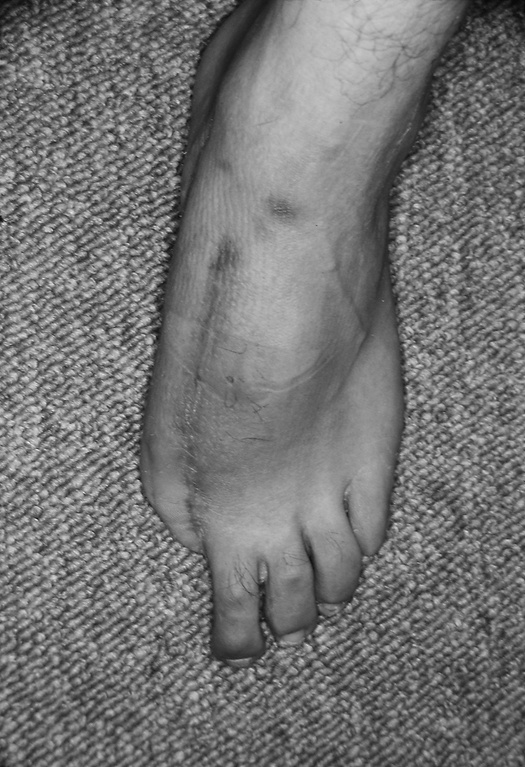

Бывает, что на одной кисти руки не хватает сразу нескольких пальцев или пациенту нужны все пальцы. В этих случаях «пригласить соседа» не получится. Если не удается «уговорить» культю вырасти, хирург может прибегнуть к «краже». Жертвой становится стопа. Большие пальцы ноги по форме почти идентичны своим собратьям на руках, поэтому именно они чаще всего идут в дело — вот только место преступления выглядит довольно неприглядно.

Если похитить второй палец ноги, замена из него получится совсем тощая, зато ступня будет иметь аккуратные очертания. Такой вариант обычно выбирают в странах, где в помещении принято снимать обувь. На способность ходить и бегать отсутствие первого или второго пальца ноги почти не влияет.

Операция по пересадке пальца с ноги на руку длится от пяти до десяти часов и требует прекрасного владения навыками микрохирургии. Хирург определяет нервы, артерии, вены и сухожилия пальца стопы, изолирует их и отрезает вместе с костью. Ампутированный палец переносят на руку и стыкуют аналогичные ткани между собой. Хирург обычно крепит кость пересаженного пальца к оставшейся в руке кости с помощью стальных штырей.

Диаметр кровеносных сосудов — от полутора до трех миллиметров: их необходимо точно соединить практически невидимыми швами, ведь кровь должна двигаться по сосудам, не просачиваясь наружу. Когда кровообращение возобновится, концы кости будут спокойно заживать, не понимая, что стопа перепуталась с кистью руки. Пройдут месяцы, в пересаженный палец врастут новые нервные волокна, и чувствительность восстановится. По-английски получившуюся комбинацию иногда называют thoe.